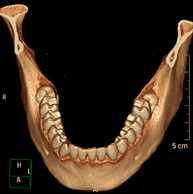

- TC Dental Prueba radiológica que consiste en obtener imágenes de los huesos maxilares de alta definición anatómica (piezas dentarias, trayecto del nervio dentario), mediante el empleo de un equipo de TC (Tomografía Computarizada). Indicaciones: estudio previo a la extracción dental, estudio previo a implantes, tumores, absceso. Prueba radiológica que consiste en obtener imágenes de los huesos maxilares de alta definición anatómica (piezas dentarias, trayecto del nervio dentario), mediante el empleo de un equipo de TC (Tomografía Computarizada). Indicaciones: estudio previo a la extracción dental, estudio previo a implantes, tumores, absceso.